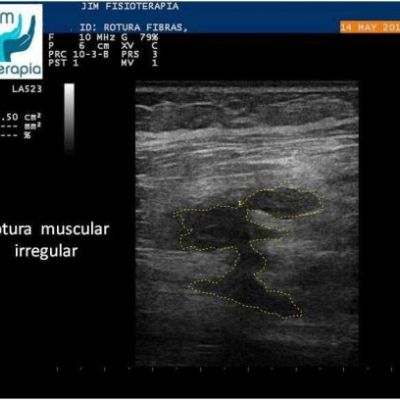

Varón de 47 años, sufre una rotura muscular en el bíceps femoral de la pierna derecha al realizar una brusca contracción excéntrica asociada a movimiento de torsión, al evitar la caída de su motocicleta. Acude a las 72 hrs a nuestra clínica presentando dolor a la palpación, contracción muscular y en la marcha. En la exploración ecográfica se observa una rotura de bordes irregulares.

Se procede a la aplicación de EPI® con el fin de “vaporizar” el derrame producido y favorecer el proceso de regeneración y cicatrización muscular sin fibrosis. En las imágenes se puede apreciar el cambio en el tejido desde la primera sesión, fueron necesarias cuatro sesiones de EPI® hasta lograr la recuperación completa, a partir de la segunda sesión el paciente refirió una desaparición del dolor en la marcha y las actividades cotidianas, complementando su tratamiento con la aplicación de Radiofrecuencia.